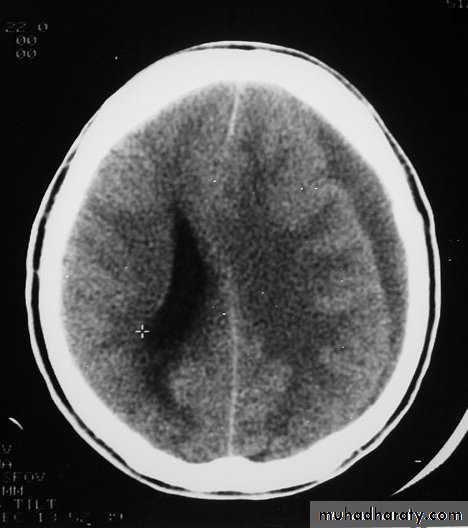

1. Brain Oedema (Cerebral Swelling)

Can be local (around a haematoma) or diffuse.

It is due to intracellular or extracellular accumulation of fluid.

It leads to raised intracranial pressure, which itself causes problems.

It is more common and more dangerous in children.